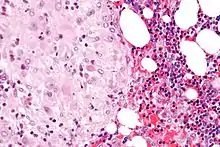

The decidua has a histologically-distinct appearance, displaying large polygonal decidual cells in the stroma. These are enlarged endometrial stromal cells, which resemble epithelium (and are referred to as "epithelioid").

Acute choriodeciduitis, with neutrophils seen in the chorion and decidua.